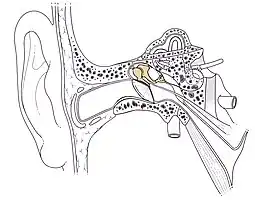

Place de la chaine des osselets dans l'oreille  Dissection d'une chaine articulaire, avec l'incus au centre